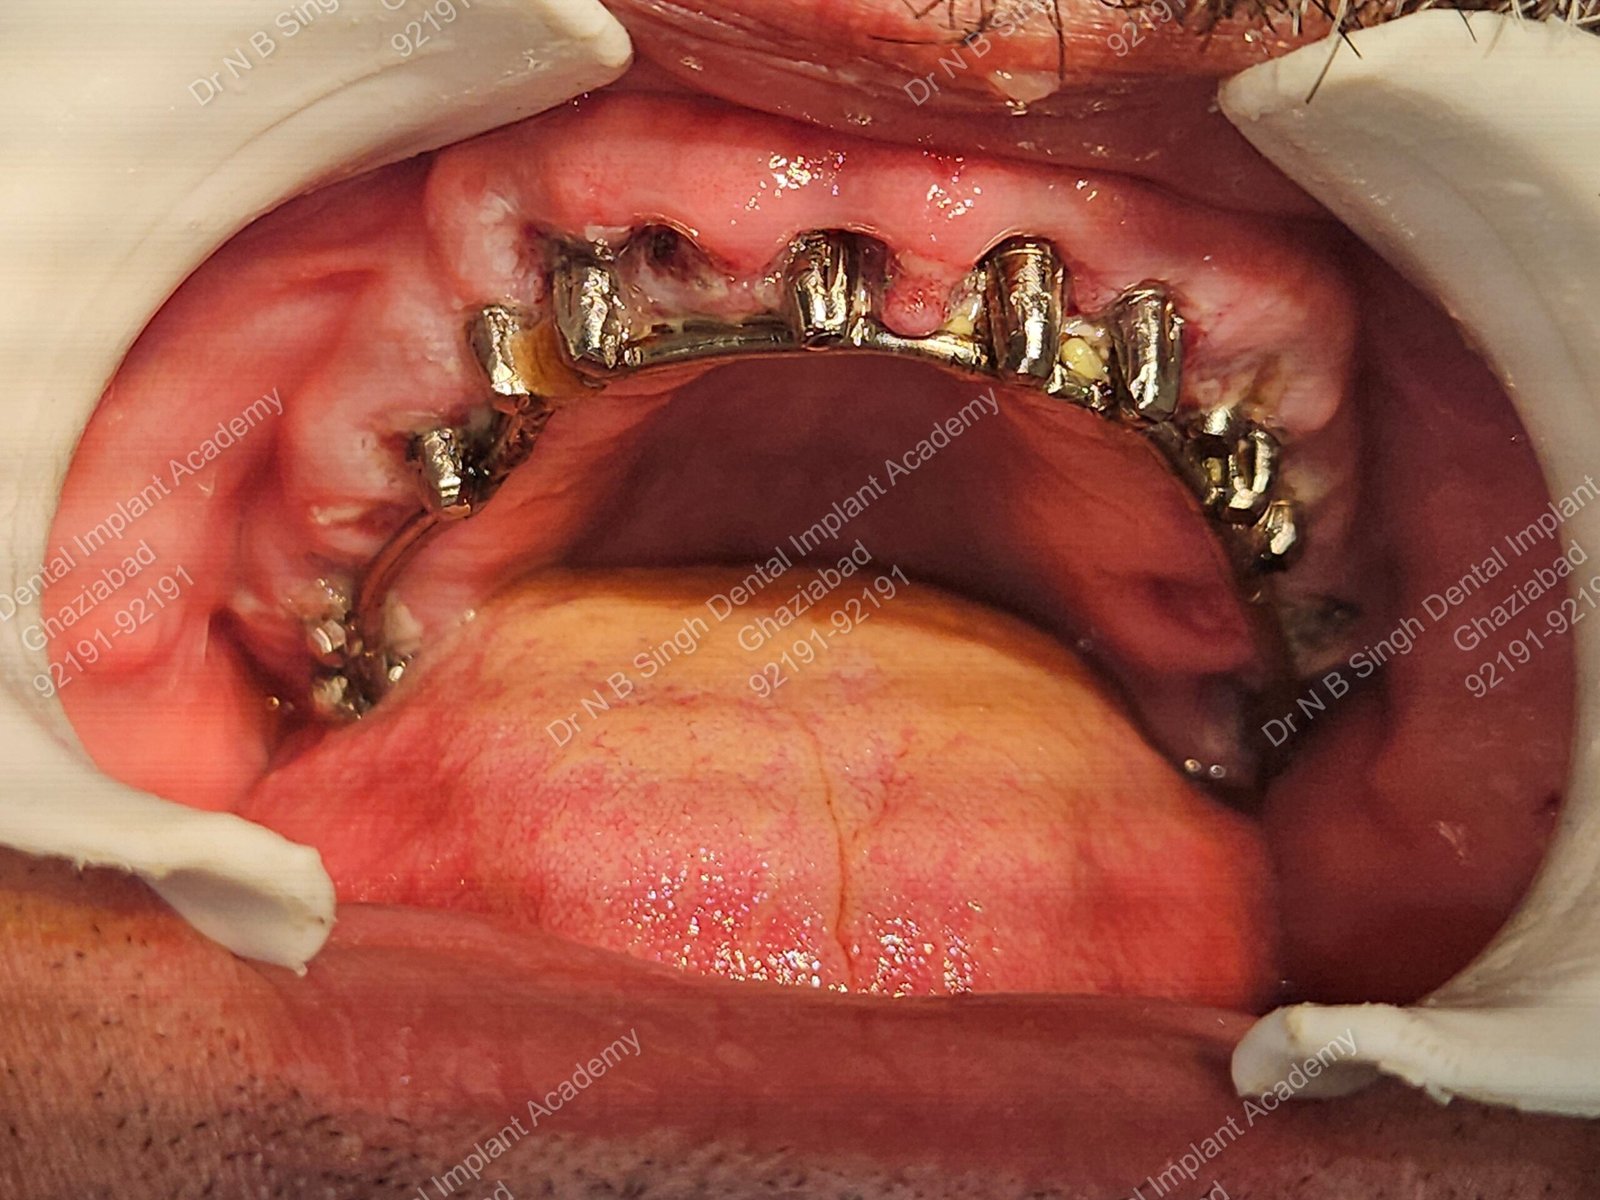

1006 Basal implant full mouth-DEEPAK

1006 -29

1006 -28